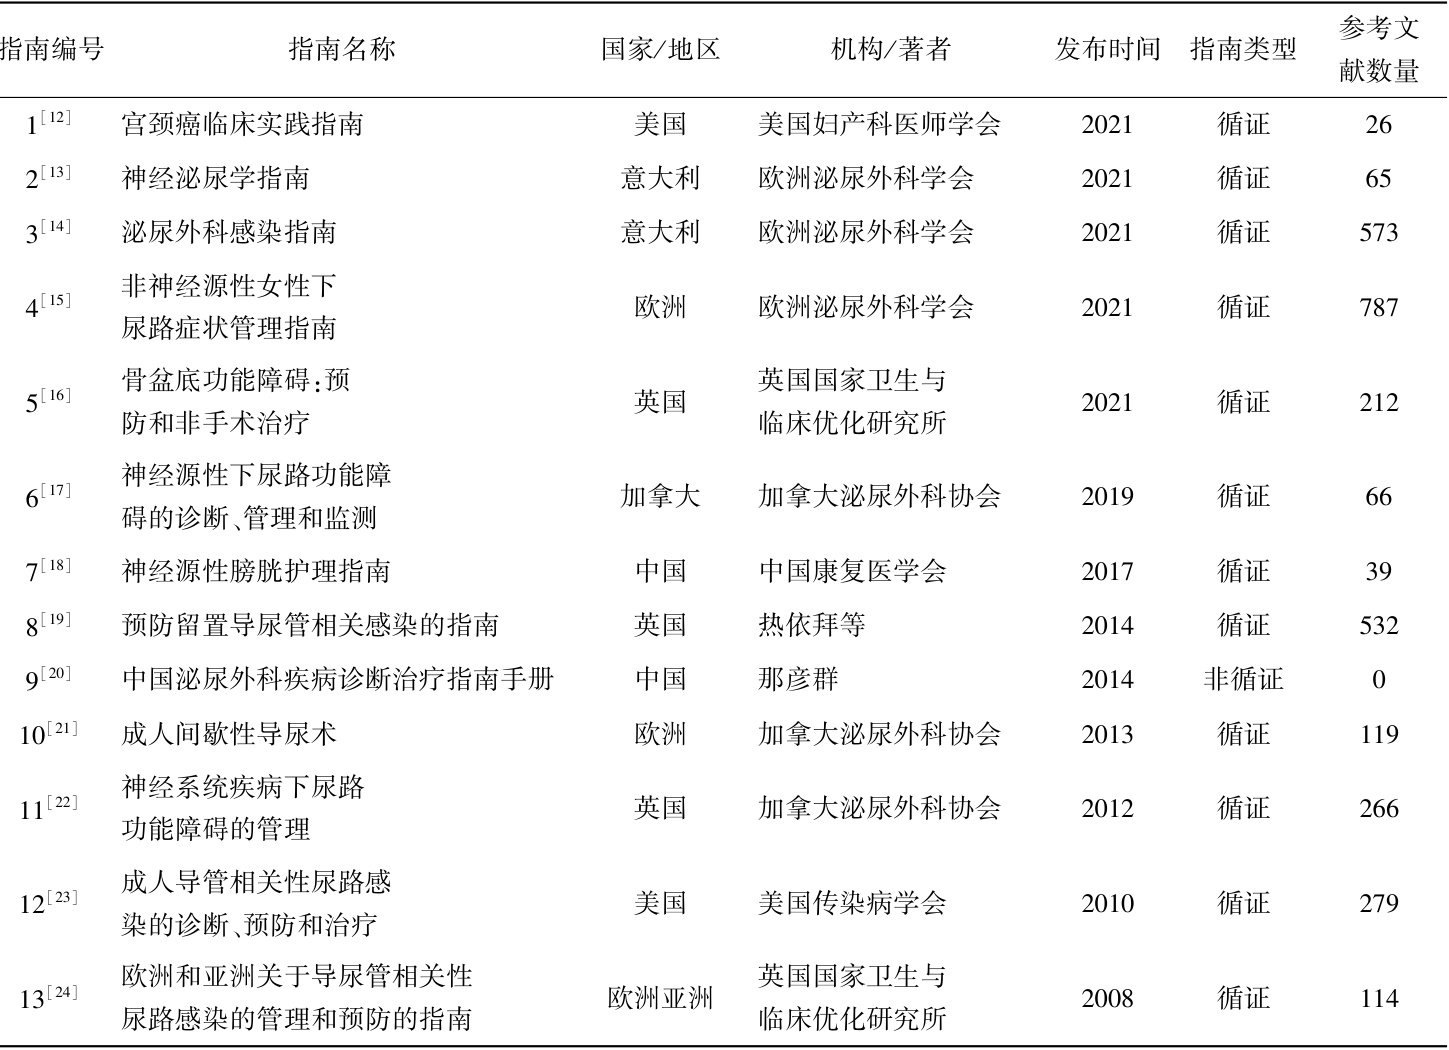

论著·临床研究 | 宫颈癌根治性子宫切除术后尿潴留管理指南的质量评价及内容分析

论著·临床研究 | 宫颈癌根治性子宫切除术后尿潴留管理指南的质量评价及内容分析